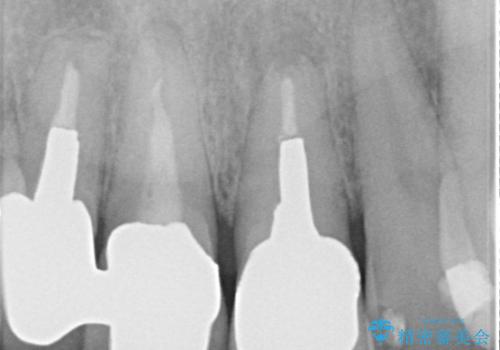

- 昔入れた前歯を綺麗にしたいことを主訴に来院された患者様です。

根尖に病変を認めたため、根管治療を行いセラミッククラウンにて修復を行なっています。

根管充填はMTAにて行なっています。